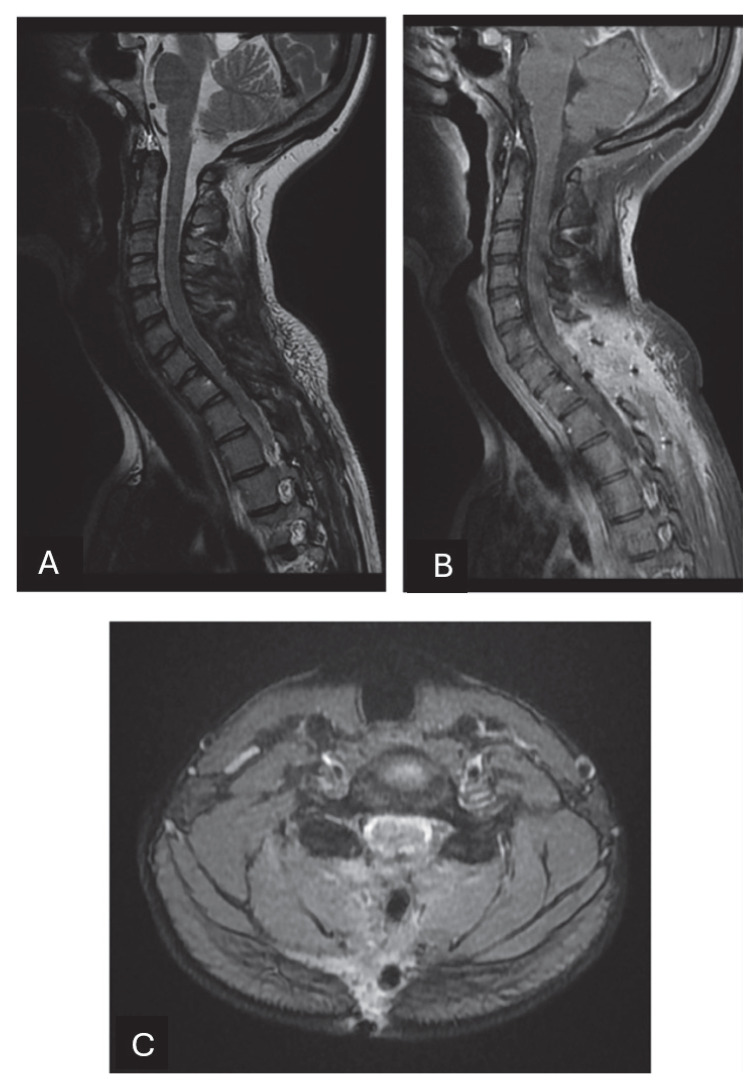

Solitary fibrous tumors (SFTs) are rare mesenchymal neoplasms of fibroblastic origin. In this study, we report a rare case of cervical SFT in a pediatric patient, a rare phenomenon since the incidence is particularly rare in pediatric patients according to the literature. Typical radiological features of the lesion may lead to misdiagnosis. Image study and immunohistochemistry are crucial for its correct diagnosis. Their imaging characteristics often resemble meningiomas or schwannomas, making differential diagnosis challenging. Immunohistochemical markers such as CD34 and STAT6 remain essential for definitive diagnosis.